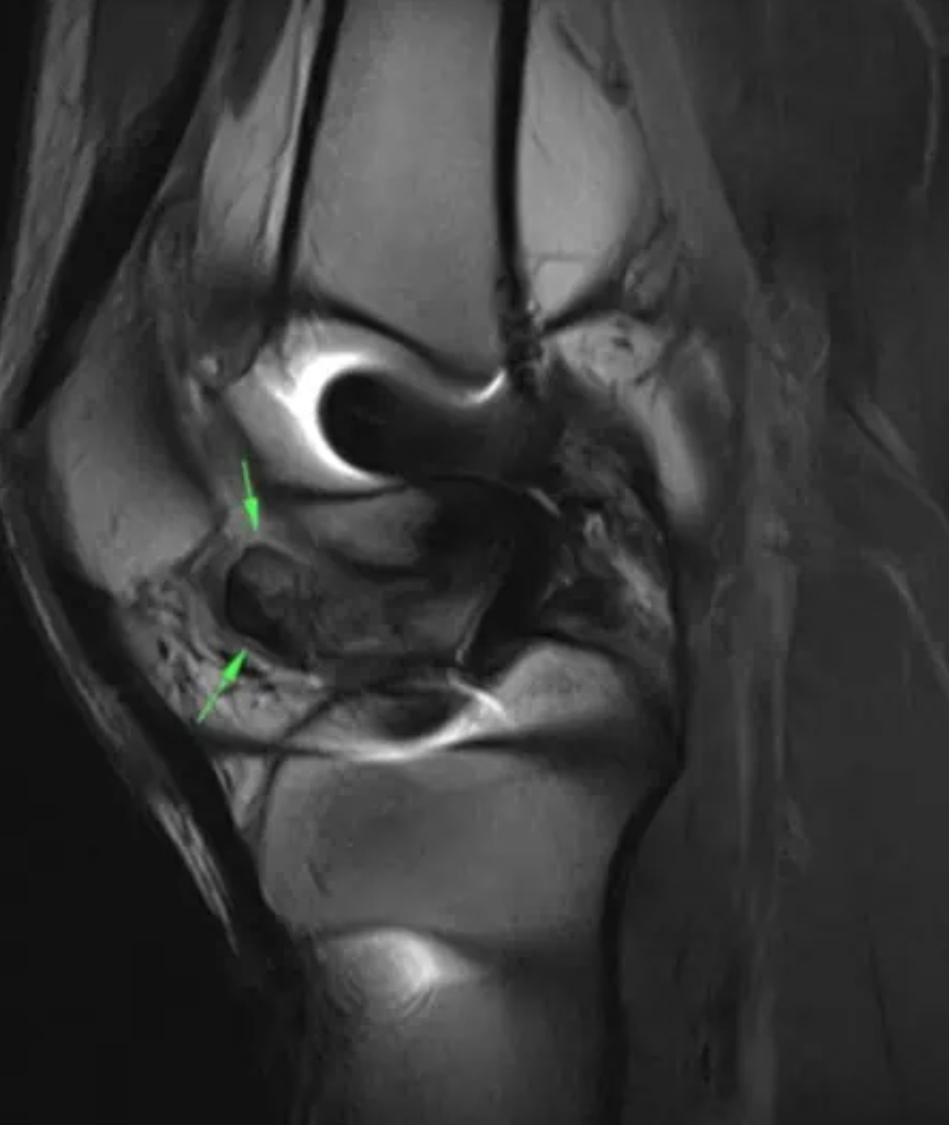

Loss of extension after ACL surgery: How to assess for a cyclops lesion